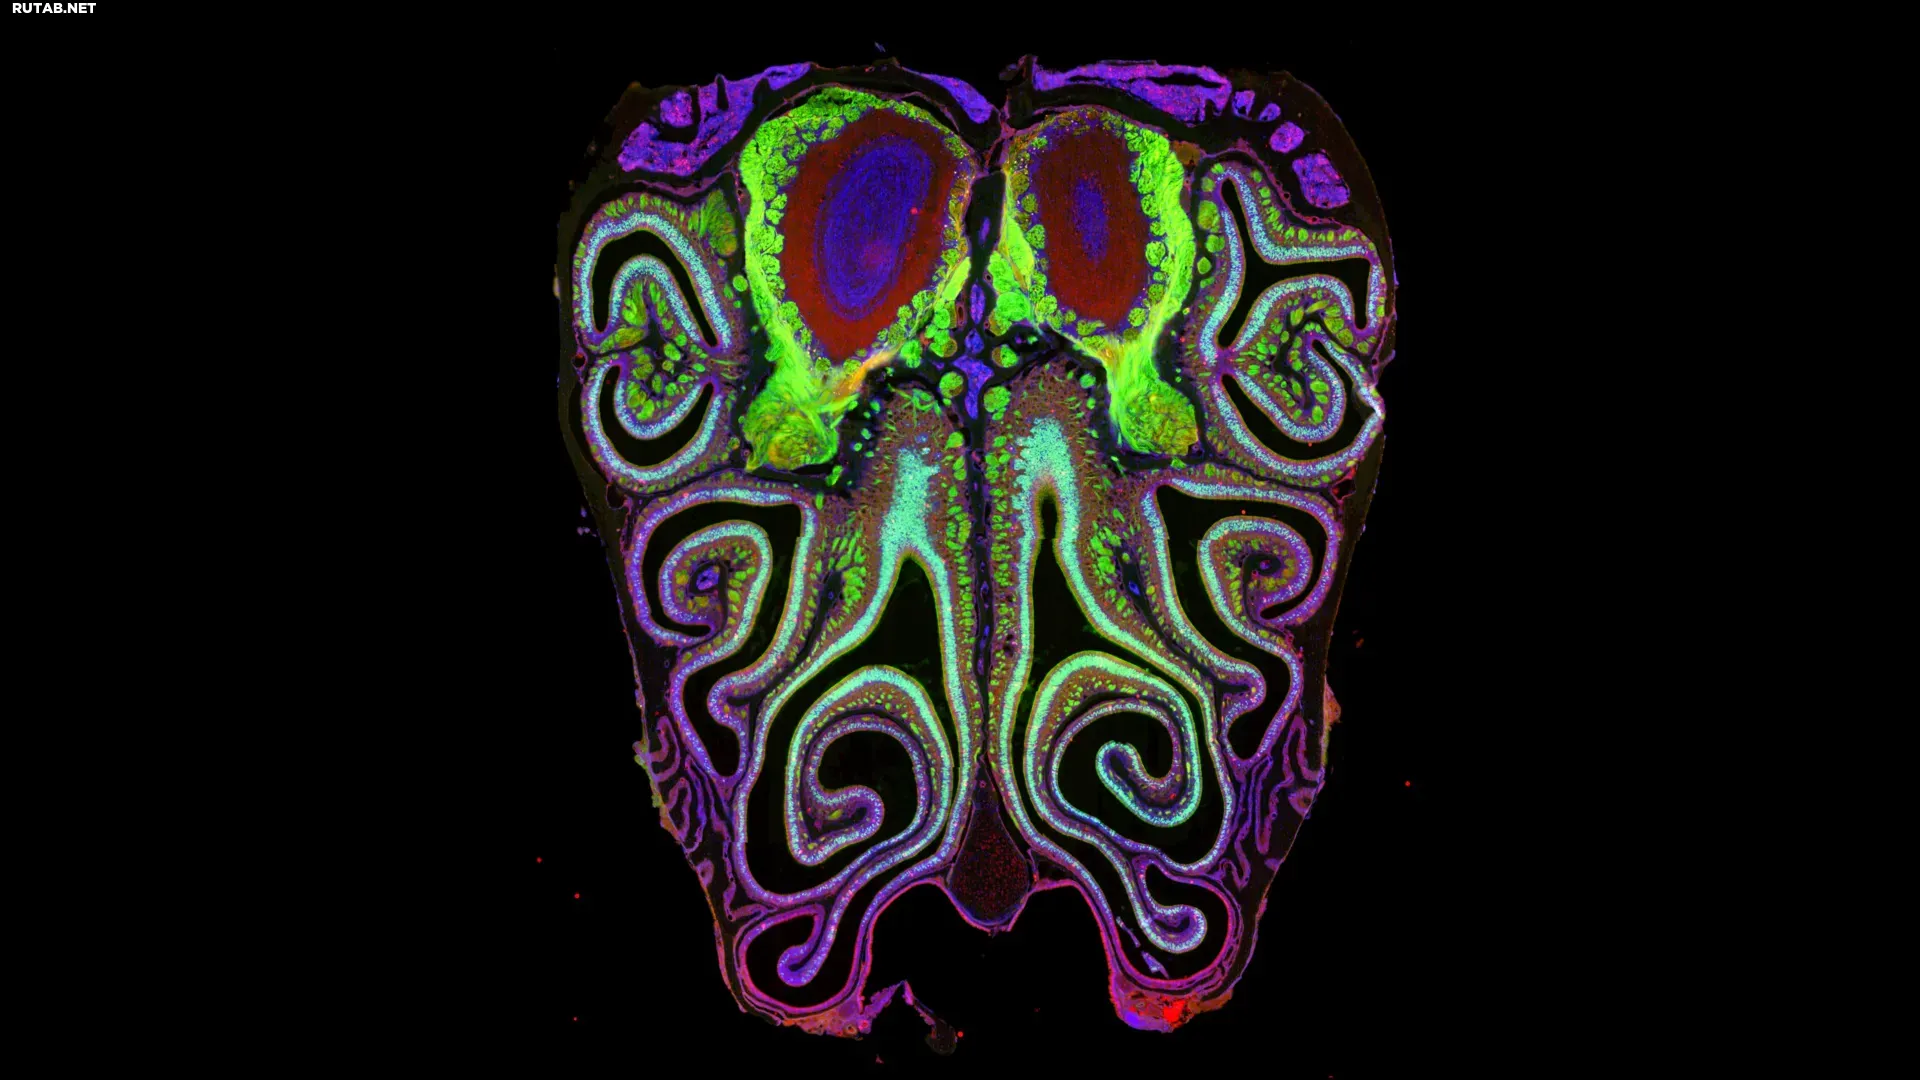

Микрофотография поперечного среза носа мыши. Мышь была генетически модифицирована для экспрессии зеленого флуоресцентного белка в обонятельных нейронах. Небольшая часть умирающих нейронов окрашена красным. Источник: Datta Lab

В новом исследовании на мышах команда Датты создала первую детальную карту расположения более тысячи типов обонятельных рецепторов внутри носа. Результаты опровергли давние предположения о том, что нейроны, несущие эти рецепторы, распределены случайным образом. Напротив, они оказались строго организованы, образуя горизонтальные полосы (стрипы) от верхней части носа к нижней, сгруппированные по типу рецептора.

Одной из причин сложности является то, что у мышей около 20 миллионов обонятельных нейронов, каждый из которых экспрессирует один из более чем тысячи типов рецепторов. Для сравнения, цветовое зрение человека опирается всего на три основных типа рецепторов. Команда проанализировала около 5,5 миллионов нейронов у более чем 300 мышей, используя секвенирование отдельных клеток и пространственную транскриптомику. Результаты выявили четкую и последовательную закономерность: нейроны образуют плотно организованные, перекрывающиеся горизонтальные полосы в зависимости от типа рецептора. Эта структура была почти идентична у всех изученных животных.